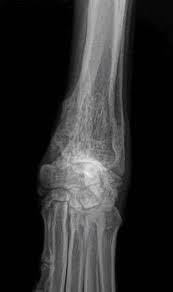

What Are The Symptoms Of Bone Cancer In A Dog : Cancer In Dogs Wikipedia : Loss of appetite and lethargy neurologic signs, such as a wobbly gait. Continuing lameness, like limping or stiffness, can be caused by nerve,. Dogs affected by myeloma show signs of general discomfort including weakness, lethargy, apathy and loss of appetite. Symptoms of bone cancer in dogs. Symptoms and diagnosis of dog bone cancer. Osteosarcoma is the most common primary bone tumor of dogs and nearly 10,000 dogs are diagnosed with this cancer each year.

Lameness that doesn't go away and swelling of the affected bone; Osteosarcomas are aggressive tumours that spread to other parts of the body (often the lungs). Types of bone cancer in dogs. It's more appropriate to call them family. This is probably due to various factors, including a higher relative risk in large and giant breed dogs to develop the disease over their lifetime (as compared to other. Our canine companions are a member of our family, making a cancer diagnosis extremely devastating. Unfortunately, symptoms can be quite ambiguous—after all, limping can have all sorts of causes. In this article we will help you understand the diagnosis of cancer in dogs. As the tumor continues to grow, the bone containing the tumor will expand. There are, in fact, several different kinds of cancer in dogs and each has a different action, set of symptoms and prognosis for the dog in question. Sometimes a biopsy is performed by taking a small piece of bone and testing it. The warning signs of cancer in dogs are very similar to that in people. The early signs of bone cancer in dogs can difficult for pet parents to recognize since symptoms tend to be subtle.

They are most common in leg bones, but can affect any bone in the body. This is often the first sign of a tumor in the skull, jaw, or ribs. The term primary bone cancer describes cancers which have their. In dogs, bone cancer also can occur as a primary or metastatic disease, but in contrast to humans, the most common form of bone cancer seen in dogs in the u.s. Usually, osteosarcoma develops in the long bones of the front legs, though the rear legs, jaw, face. As you can imagine, as bone cancer progresses, it is extremely painful for dogs, and the pain can cause other problems such as: Continuing lameness, like limping or stiffness, can be caused by nerve,. These are the most common symptoms when a tumor affects a limb. Unfortunately, symptoms can be quite ambiguous—after all, limping can have all sorts of causes. Unfortunately, the symptoms of bone cancer can be subtle and hard to detect at. Symptoms of bone cancer in dogs. Osteosarcomas are painful tumours that often first appear as hot, solid, tender swellings. Symptoms of bone cancer the most common symptom associated with osteosarcoma is lameness.

Symptoms of bone cancer because early diagnosis and treatment is essential to prolonging your dog's life, you should be aware of the early signs of bone cancer and bring your dog to the vet as soon as they occur. This is probably due to various factors, including a higher relative risk in large and giant breed dogs to develop the disease over their lifetime (as compared to other. Bone cancer is a broad term which loosely defines the basics of the disease. Dressler explains why they don't typically wait for a biopsy. Below are some of the most common symptoms of bone cancer that pet parents should watch for: In dogs, bone cancer also can occur as a primary or metastatic disease, but in contrast to humans, the most common form of bone cancer seen in dogs in the u.s. Sometimes a biopsy is performed by taking a small piece of bone and testing it. Bone cancer is also accompanied by a lot of swelling. There are, in fact, several different kinds of cancer in dogs and each has a different action, set of symptoms and prognosis for the dog in question. Bone cancer in dogs osteosarcoma is the most common type of bone cancer in dogs. Canine bone cancer symptoms osteosarcoma tumors typically form in a dog's long bones, or growth bones, and are found frequently below the elbow or near the knee or shoulder. Unfortunately, the symptoms of bone cancer can be subtle and hard to detect at. Bone cancer in dogs also seems to happen either early or later in life.